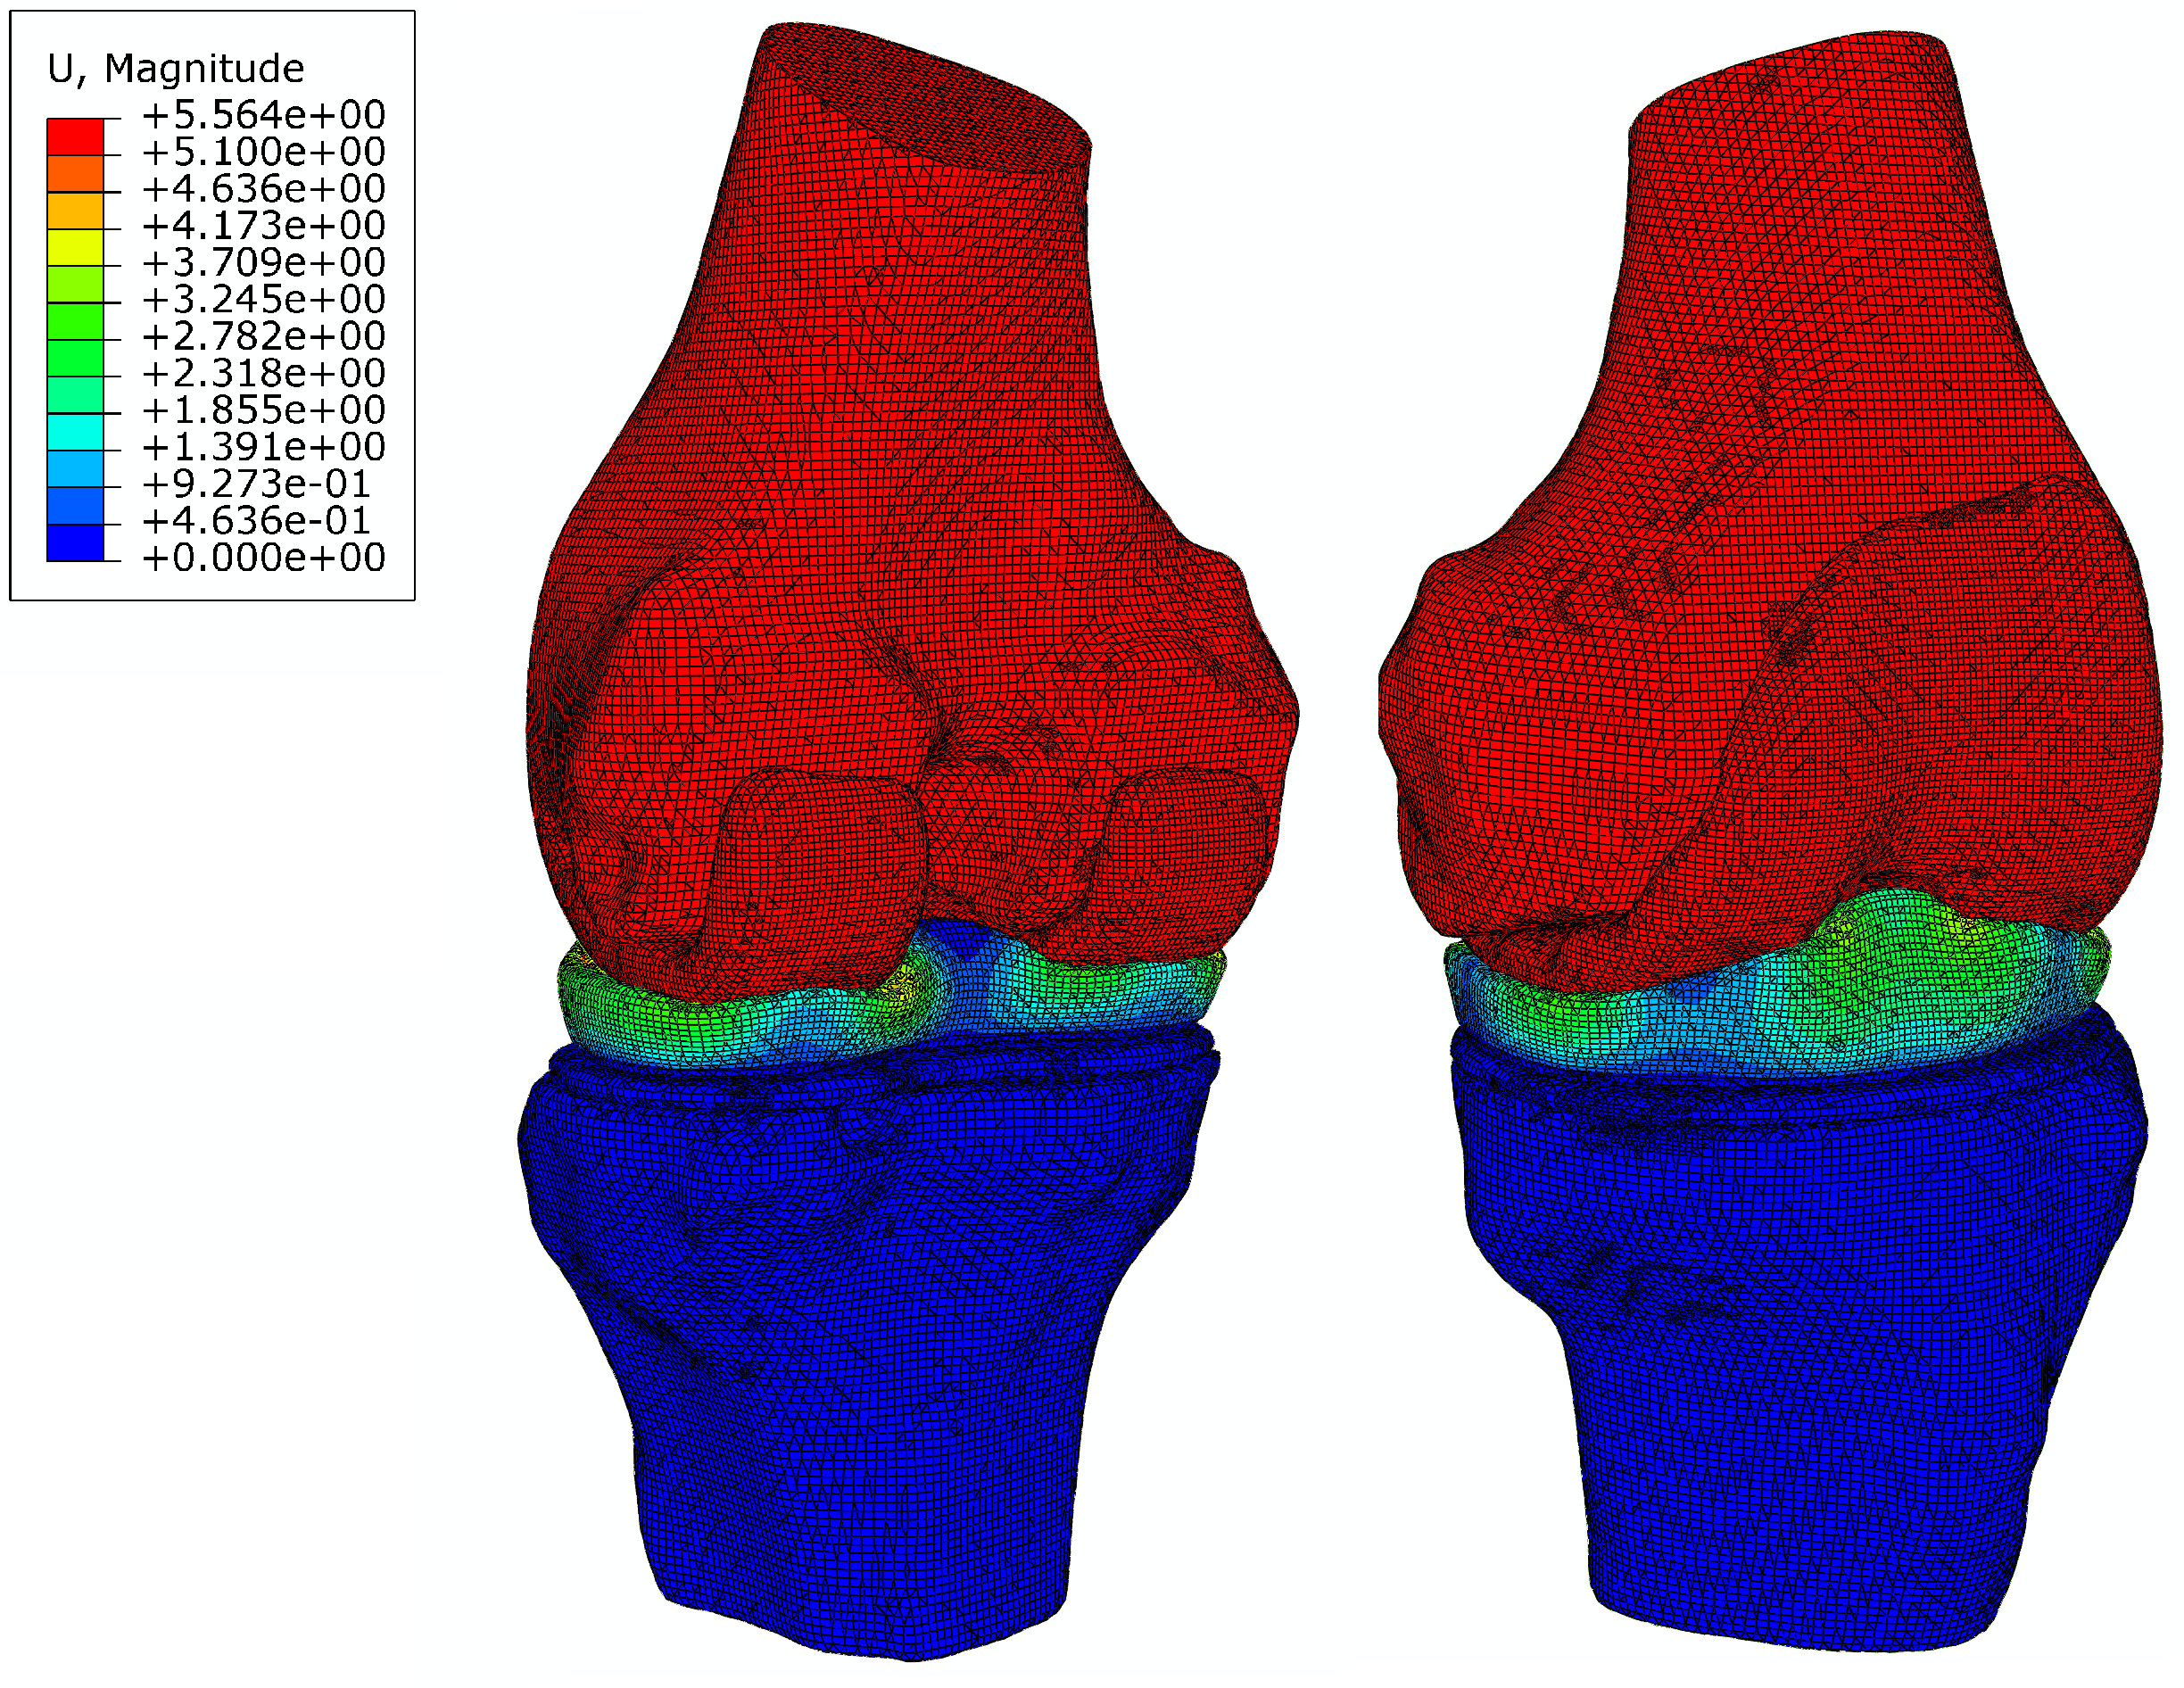

4.3.2 Analysis of a knee joint

A knee joint given in STL format [70] is considered for performing a contact analysis. The knee joint is composed of femur and tibia, a meniscus and two articular cartilages as illustrated in Fig. 30. The femur and the tibia are covered with articular cartilages, thus the interactions between bones and articular cartilages can be treated as perfect bond (tie constraint in ABAQUS). The meniscus is inserted into the articular cartilage covering the tibia, thus the interaction between them can also be regarded as perfect bond. The interaction between the meniscus and the articular cartilage covering the femur is treated as contact.

The mesh generated by the octree algorithm with trimming [29] is shown in Fig. 31. The base sizes are and for the contact parts and other parts, respectively. There are 253,079 elements and 361,296 nodes, and the number of nodes in one element varies from 4 to 27. A slice in the vertical plane passing the geometrical center is also shown in Fig. 31. The contact interface meshes are non-matching for this example, because the contact domains are geometrically non-conforming and large sliding might occurs at the interface during the loading process. The meshes generated through the STL-based octree algorithm are suitable for contact analysis. In the standard FEM, local mesh refinement may be required to generate finer meshes on the contact surfaces. However, in an automatic manner, octree cells with fast mesh size transition can be generated through the octree mesh generation technique. Compared to the interior elements, the elements near the boundaries are smaller, which will generate more accurate surfaces for tie constraints and contact pairs. Besides, compared to the image-based technique, the STL-based octree algorithm allows trimming on the octree cells, which leads to more accurate meshes representing complex boundaries especially for curved shapes.

The tissue material properties in the computational modeling of human knee joints have been studied in Ref. [71], however, there are considerable variations of the material properties within the wide body of literature. The mechanical properties used in this example are mainly taken from Ref. [72] and are listed in Table 9. The contact is STS contact with a friction coefficient of [73].

| Femur | Tibia | Articular cartilage | Meniscus | |

|---|---|---|---|---|

| Young’s modulus | ||||

| Poisson’s ratio | 0.2 | 0.2 | 0.25 | 0.35 |

The bottom surface of the tibia head is fixed, and two translational DOFs in the horizontal plane of the top surface of the femur head are also constrained. On the top surface of the femur head, a vertical load of up to [72] is applied to induce contact in the knee joint. The displacement contours () from different views are shown in Fig. 32. It is obvious that the deformation occurs mainly in the meniscus. The femur, tibia and articular cartilages are similar to rigid bodies. This phenomenon meets the expectation because the Young’s modulus of the meniscus is significantly smaller than those of the bones and articular cartilages. The meniscus is squeezed into the joint space and there is lateral extension of the meniscus. The large deformation of the meniscus increases the contact area which is helpful to reduce the contact pressure.

The contact pressure distributions () are depicted in Fig. 33. To illustrate the distribution clearly, contact pressure values smaller than are not included in the contour. It is obvious that the contact pressure on the articular cartilage has a similar distribution and magnitude compared to that on the meniscus. Besides, the contact pressure on the articular cartilage has a similar distribution from Ref. [72].

The development of the contact on the articular cartilage is recorded, as depicted in Fig. 34. Note that only the area where the contact pressure is greater than has been taken into account. Generally speaking, with increasing the vertical load , the contact area is increasing while its increasing rate is reducing. The average contact pressure increases during the loading history. Before the vertical load increases up to , the increasing rate of the average contact pressure is basically reducing. However, when the average contact pressure increases almost linearly because the contact area increases only slightly.

The total CPU time of this example is 16.68 hours, in which 0.90 hours are spent on the element analysis of UEL. The UEL time comprises of 0.52 hours on the pre-calculation and 0.38 hours on the step of nonlinear analysis. It accounts for only 5.4% of the total CPU time.